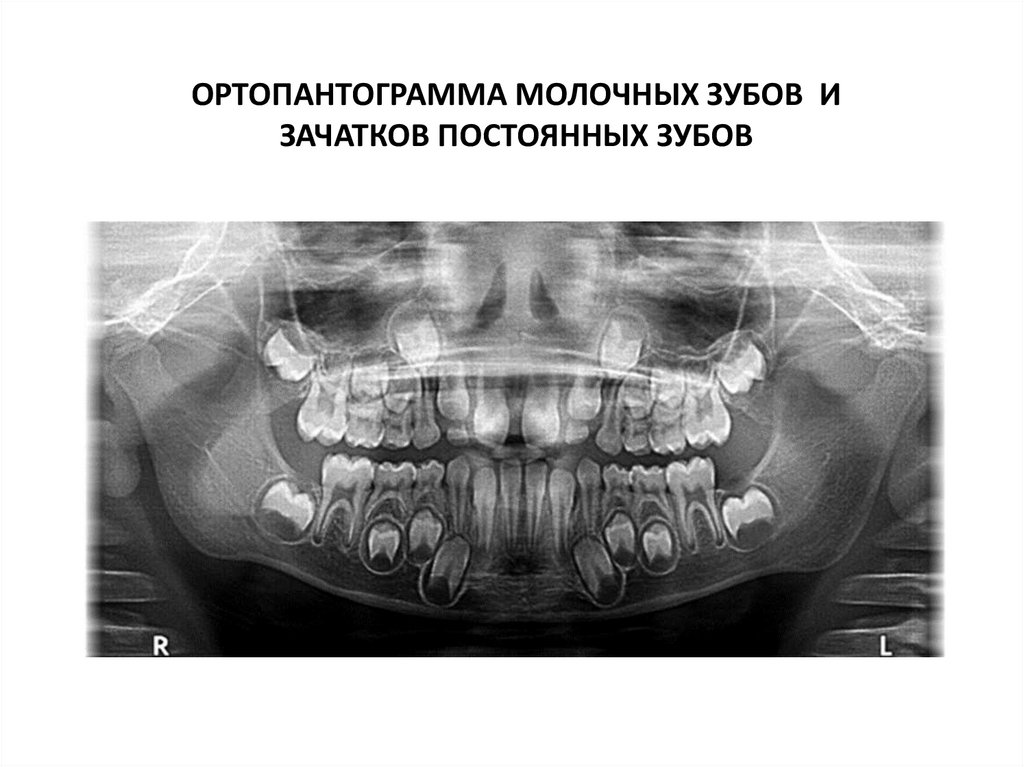

ОРТОПАНТОГРАММА МОЛОЧНЫХ ЗУБОВ И

ЗАЧАТКОВ ПОСТОЯННЫХ ЗУБОВ

103.